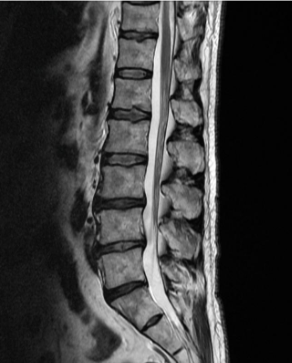

허리디스크 증상 치료방법 및 수술비용에 대해 알아보겠습니다. 허리디스크는 척추 뼈 사이에 있는 디스크가 손상되어 신경을 압박하는 질환입니다. 디스크는 척추뼈 사이의 충격을 흡수하고 척추의 움직임을 부드럽게 해주는 역할을 하는데, 이 디스크가 손상되면 신경을 압박하여 통증, 마비, 감각 이상 등의 증상이 나타납니다. 허리디스크는 흔히 40~50대 중년층에서 발생하지만, 젊은 나이에도 발생할 수 있습니다.

허리디스크의 치료방법은 증상의 심각성과 개인의 상황에 따라 다르게 선택됩니다. 일반적으로는 비수술적 치료가 우선적으로 시도되며, 수술적 치료는 보존적 치료로 증상이 호전되지 않거나 신경마비가 있는 경우에 고려됩니다.

허리디스크 수술의 종류에는 여러 가지가 있습니다. 가장 일반적인 수술은 개방적 수술로, 척추를 접근하기 위해 피부와 근육을 절개하고, 디스크가 탈출한 부분을 직접 제거하는 방법입니다. 이 수술은 전신마취로 진행되며, 수술 시간은 1~2시간 정도 소요됩니다. 개방적 수술의 장점은 디스크를 완전히 제거할 수 있고, 재발률이 낮다는 것입니다. 단점은 상처가 크고, 출혈이 많고, 감염 위험이 있으며, 회복 기간이 길다는 것입니다.